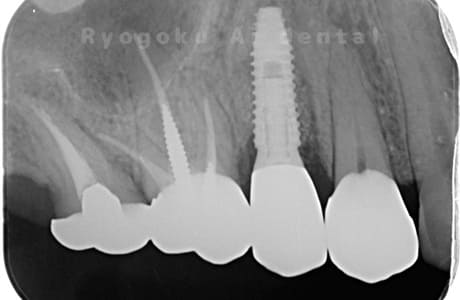

Case07

- 原因

- 右下6番歯根破折

-

- 治療内容

- インプラント治療

- 治療費用

- 約600,000円

右下の腫れが治らないとの事でご来院された患者様です。歯が割れていたため、抜歯を行い、骨に代わるお薬を入れ、インプラントを埋入致しました。経過良好で大変満足していただけました。

<リスク・副作用>

治療後、痛みや違和感、出血、腫れなどが出る事があります。喫煙者、糖尿病などの方の場合、歯が生着しない場合があります。